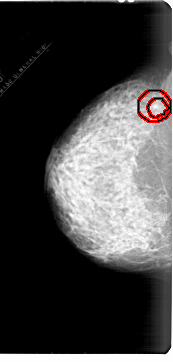

A_1878_1.LEFT_MLO

LEFT_MLO LINES 6496 PIXELS_PER_LINE 3316 BITS_PER_PIXEL 12 RESOLUTION 43.5 OVERLAY

FILE: A_1878_1.LEFT_MLO.OVERLAY

TOTAL_ABNORMALITIES 1

ABNORMALITY 1

LESION_TYPE MASS SHAPE IRREGULAR MARGINS SPICULATED

ASSESSMENT 4

SUBTLETY 1

PATHOLOGY BENIGN

TOTAL_OUTLINES 1

BOUNDARY